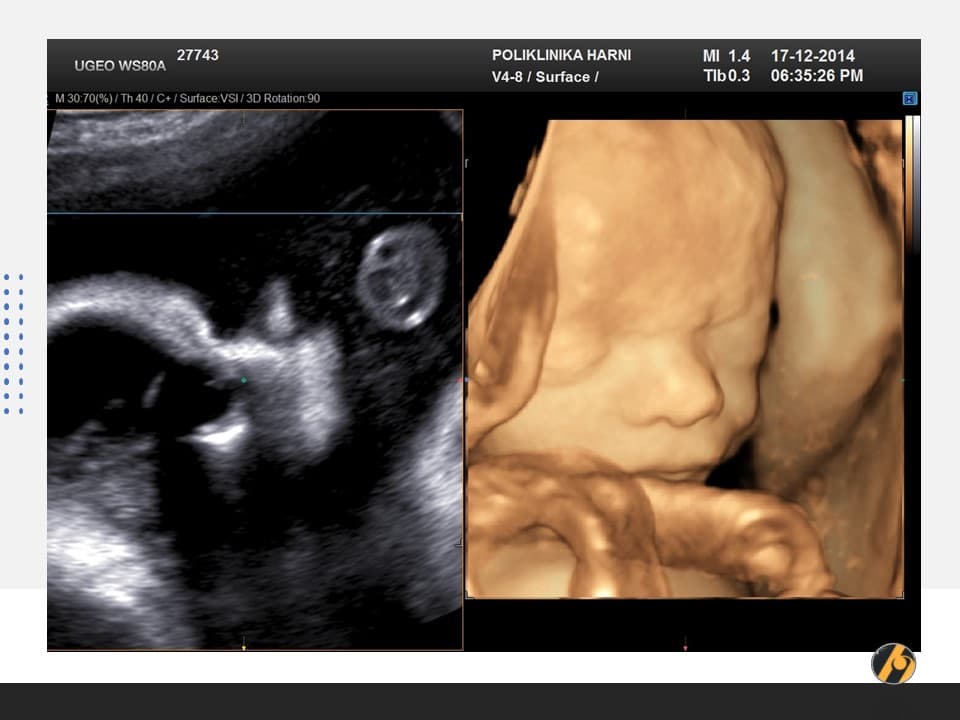

Vaša beba dugačka je oko 43 cm, a teška 2,000 – 2,250 g.